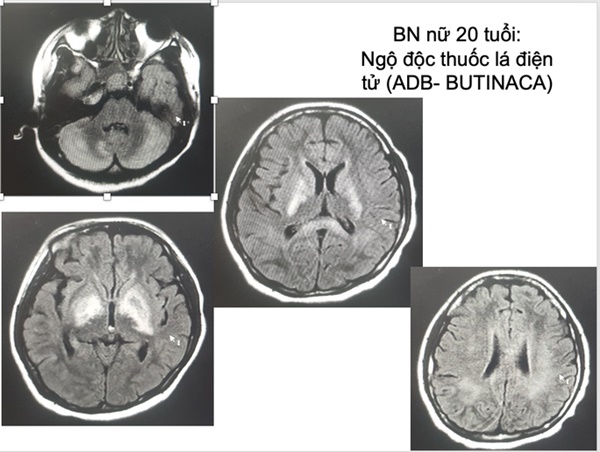

Tiến sĩ-bác sĩ Nguyễn Trung Nguyên, Giám đốc Trung tâm Chống độc, Bệnh viện Bạch Mai, cho biết thời gian qua trung tâm tiếp nhận rất nhiều trường hợp ngộ độc do sử dụng thuốc lá điện tử. Điển hình là nữ bệnh nhân 20 tuổi ở Hà Nội được đưa vào cấp cứu trong tình trạng hôn mê sâu, suy tim, tổn thương não, tổn thương gan… do hút thuốc lá điện tử.

Bệnh nhân nhập viện trong tình trạng nguy kịch do tổn thương và suy nhiều cơ quan, trong đó nặng nhất là tổn thương não lan tỏa tại tất cả các vị trí. Ngoài ra, bệnh nhân còn bị tổn thương và suy tim nặng, suy thận, tổn thương gan...

Hình ảnh tổn thương não của nữ bệnh nhân 20 tuổi. Ảnh: Bác sĩ cung cấp